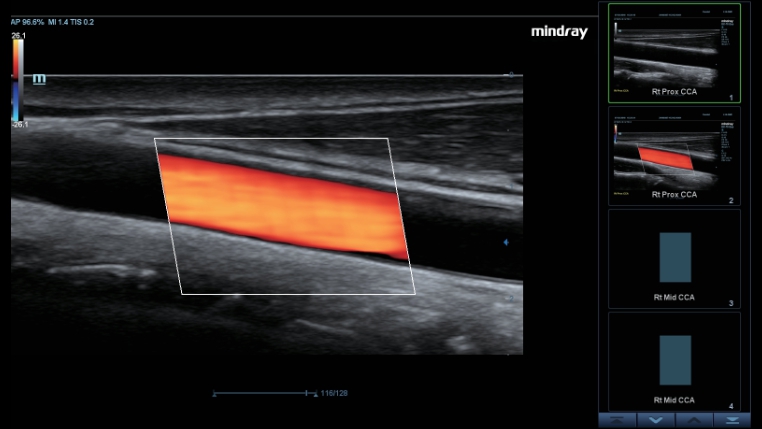

ComboWave transducers

In tegenstelling tot traditionele transducers gebruiken de ComboWave-transducers een nieuw type samengesteld pi?zo-elektrisch materiaal om het akoestische spectrum drastisch te optimaliseren en de akoestische impedantie te verminderen. De lineaire transducers van ComboWave, die verder zijn ge?ntegreerd met de unieke 3T-technologie van Mindray, stellen u in staat uitstekende prestaties te ervaren met een extreem hoge beeldresolutie en uniformiteit in de schildklier, borst, vaten en meer.

Smart Track biedt snelle en intelligente optimalisatie voor vasculaire beeldvorming met slechts ├®├®n druk op de knop. Het optimaliseert het kleuren-, power- en PW-spectrum met zelftracking en reduceert het aantal tijdrovende stappen. De workflow voor vasculair onderzoek wordt daarmee vereenvoudigd met een optimale weergave.